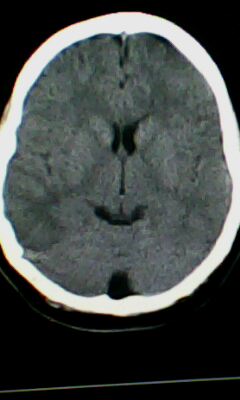

颅脑ct轴位平扫颅内未见明确异常。

脑皮质增厚,发育异常!

左侧灰质异位

建议mri

颅脑ct轴位平扫颅内未见明确异常,建议mri。